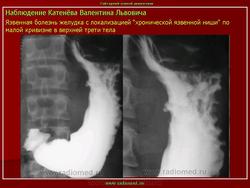

Этим термином обозначают тень контрастного вещества, проникшего в язвенный кратер. Силуэт язвы может быть виден в профиль, и тогда говорят о контурной нише (рис. 45, а). Однако язва может быть видна в анфас на фоне складок слизистой оболочки, и в этих случаях ее именуют нишей рельефа, или рельефной нитей (рис. 45, б). Рельефная ниша имеет вид округлой или овальной тени, а при неполном заполнении язвы - форму кольца. Язвы тела желудка обычно удается сделать краеобразующими и получить симптом контурной ниши. При выявлении язв антрального отдела это не всегда возможно, поэтому в этих случаях особое значение приобретает симптом рельефной ниши (рис. 46).